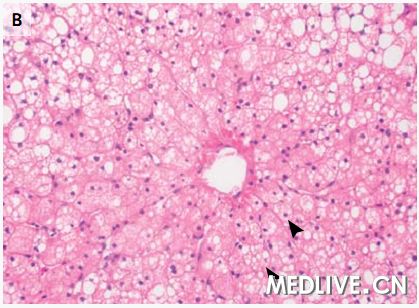

体格检查,患儿倦怠,间歇性不安,并且啜泣。体重是8.9 kg(相应年龄的第25至第50百分位数),体温37.6°C,血压95/46 mgHg,脉率133次/分;呼吸率26次/分,以及在他呼吸周围空气时的氧饱和度为100%。结膜苍白、无黄疸。左眼上方有一块瘀伤。肠鸣音减弱,腹软,无压痛或膨隆。肝边缘延伸至肋缘下4 ~ 5 cm。其余检查均正常。镁、C反应蛋白、淀粉酶、脂酶、铁、总铁结合力和乳酸盐水平均正常;其他结果显示于表1。尿液分析正常,尿液毒物筛查阴性。腹部X线检查显示非特异性肠内积气征,没有游离气体或肠梗阻的证据。给予静脉液体输入。没有使用对比剂的脑部计算机体层摄影(CT)检查正常。腹部的超声检查显示肝脏回声略微增强,并且胆囊周围有液体,没有肝内或肝外胆管扩张的证据。

图1 腹部成像检查 右肝叶矢状面超声图像(图A)显示,与邻近的肾脏相比,肝实质回声增强,这与脂肪浸润(的表现)一致。腹部轴向计算机体层摄影图像(图B)显示,弥漫性肝脏密度降低,这也与脂肪浸润(的表现)一致。

奥托·拉帕利诺医师:入院时进行的腹部超声显示肝实质回声弥漫性增强,符合脂肪浸润,没有局灶异常,并且胆囊周围有少量液体(图1A)。为了进一步评估肝脏而进行的腹部CT检查显示,肝实质脂肪性衰减,轻度肝肿大,以及胆囊周围有少量液体(图1B)。